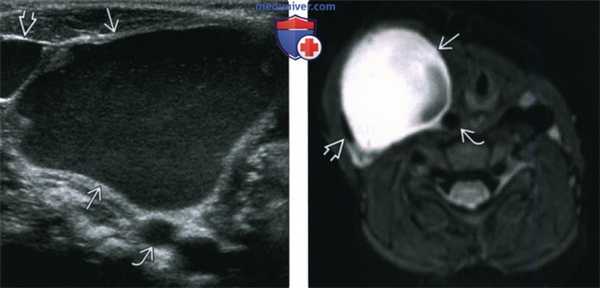

(Слева) На поперечной сонограмме у ребенка в возрасте 16 месяцев визуализируется крупное однокамерное кистозное образование с большим количеством эхогенных включений внутри, подвижных при исследовании в реальном времени. Образование отодвигает яремную вену и сонную артерию в разные стороны, что является признаком, типичным для кисты тимуса. Тем не менее, макрокистозная лимфатическая мальформация может выглядеть также.

(Справа) При аксиальной MPT FSE у этого же пациента визуализируется объемное образование с гиперинтенсивным сигналом, смещающее правую яремную вену и сонную артерию в разные стороны друг от друга, что характерно для кисты тимуса.